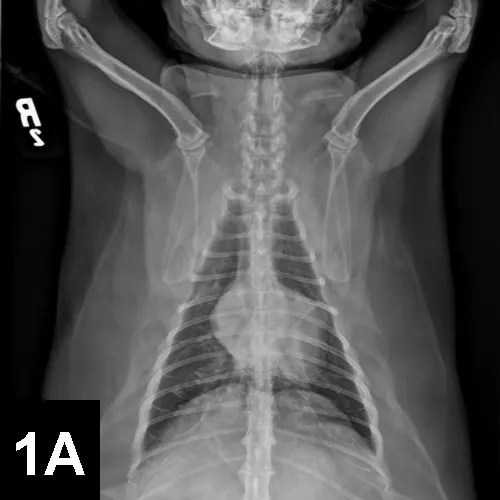

DIAGNOSTICSDual-view radiographs (see Figure 1 below) and an ECG (see Figure 2 below) were obtained at presentation.

Figure 2. Lead II ECG (50 mm/sec; standard sensitivity) with the cat in right lateral recumbency. The heart rate is 230 beats/min, which is faster than the rate during examination, likely due to stress from being restrained for the ECG.

• The extra heart sound on examination may have represented a diastolic gallop, as it was diastolic and of low frequency, which can indicate cardiac diastolic dysfunction. The ECG revealed sinus rhythm (heart rate, 230 beats/min) and increased R-wave amplitude (2.1 mV; normal <0.9 mV), which suggest left ventricular hypertrophy. The radiographs revealed generalized cardiomegaly, left atrial enlargement, distended and prominent pulmonary vasculature, and cardiomegaly with a patchy interstitial pattern. This combination of findings is most consistent with cardiogenic pulmonary edema.